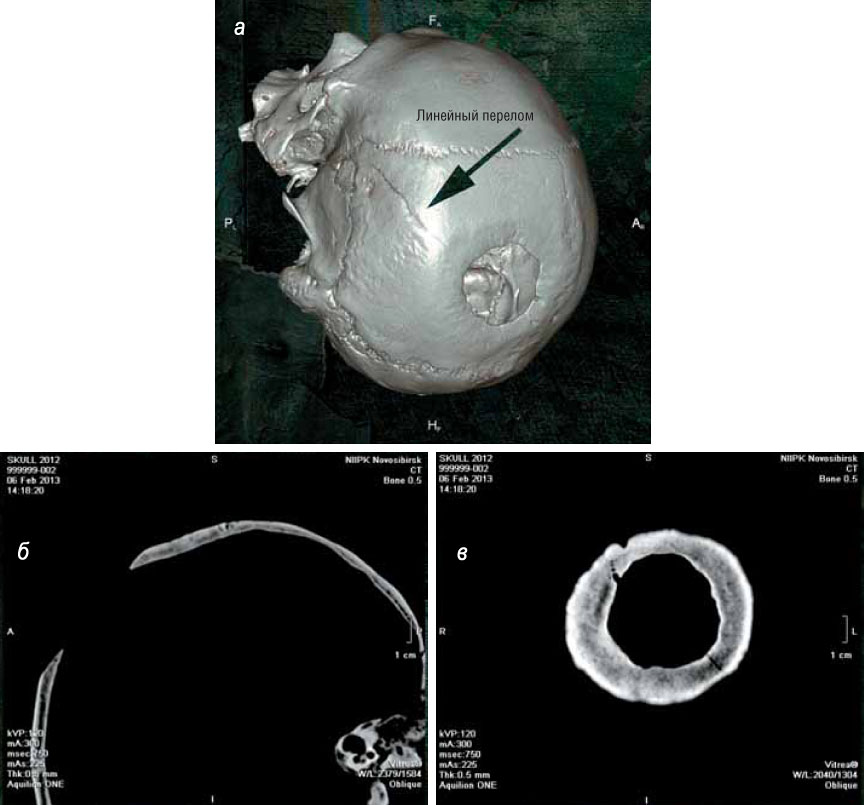

На черепе мужчины из кургана 3 комплекса Кызыл-Джар V размеры трепанационного окна составляют 40×41 мм. Край дефекта скошен за счет того, что была удалена часть наружной пластинки, и в результате общие размеры костного дефекта составляют 63×64 мм. В данном случае операция проводилась для устранения в левой височной и теменной кости линейного перелома, идущего до сагиттального шва. По современным стандартам нейрохирургии, выполнена она была блестяще: как показала МСКТ, в месте перелома произошла регенерация костной ткани.

На черепе мужчины из кургана 3 курганной группы Кызыл-Джар V обнаружено трепанационное отверстие размером 63×64 мм, а также следы успешно залеченного линейного перелома костей. Череп хранится в антропологической коллекции Томского государственного университета

По характеру перелома, идущего на сагиттальный шов, под которым располагается сагиттальный синус — крупный венозный коллектор, можно с большой вероятностью подозревать, что у пациента развилась эпидуральная гематома вследствие травматического разрыва края синуса, и целью операции было ее удаление. В этом смысле отверстие имеет оптимальные размеры — при выполнении подобной операции даже современный хирург не сделал бы его меньше.

Результаты обследования черепа мужчины из кургана 3 курганной группы Кызыл-Джар V методом МСКТ: а — объемная модель черепа; б — срез через трепанационный дефект в боковой проекции; в — горизонтальный срез через поверхность трепанационного дефекта